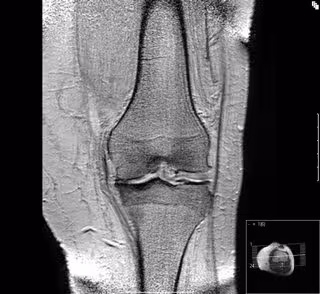

Investigadores de Suiza, Canadá y Estados Unidos han diseñado unos zapatos con una suela biomecánica que reduce significativamente el dolor asociado con la artrosis de rodilla, según publican en línea en la revista 'JAMA'.

La artrosis de rodilla afecta aproximadamente a 275 millones de personas en todo el mundo y en 2017 se estimó que representaba 8,3 millones de años con discapacidad. El acetaminofeno, los medicamentos antiinflamatorios no esteroideos y los opioides son los medicamentos más utilizados para tratar el dolor, pero tienen una eficacia limitada.

Investigadores de la Facultad de Medicina de la Universidad de Boston (BUSM), la Universidad de Toronto y la Universidad de Berna (Suiza) han realizado un ensayo clínico con 220 participantes que sufrían de artrosis dolorosa. La mitad probó el calzado biomecánico mientras que los del grupo de control usaban los zapatos normales.

Después de seis meses el grupo biomecánico tuvo una disminución mayor en su puntuación de dolor medido por la escala de dolor del Índice de Artrosis del Oeste de Ontario.

"Estos hallazgos proporcionan una fuerte evidencia que respalda la efectividad de un nuevo tratamiento para la artrosis de rodilla", asegura David Felson, profesor de Medicina en BUSM y coautor del estudio. Felson, reumatólogo del Boston Medical Center, cree que el tratamiento probablemente funciona reeducando y reacondicionando los músculos de las piernas. "Este tratamiento puede ayudar a muchas personas con este trastorno", afirma.

Según los investigadores, no solo parece reducir el dolor en los pacientes, sino que también puede ser efectivo para algunas personas con dolor de cadera o espalda. No obstante, advierten de que se necesita más investigación para evaluar la eficacia y seguridad a largo plazo.